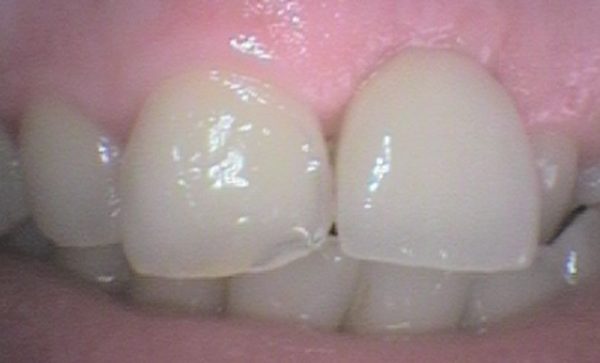

Case 17